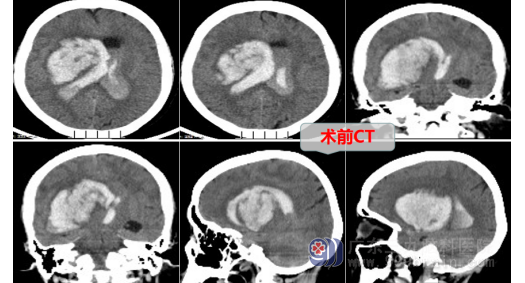

张阿姨发病前,突然出现左侧肢体无力,进行性加重,到当地医院就诊,头部CT检查提示右侧基底节梗死,医生即给予急诊行尿激酶溶栓治疗,术后张阿姨意识障碍不但没好转,反而进行性加重。晚上,急救车来到广东三九脑科医院时,张阿姨已经是昏迷状态,脑疝形成,GCS3分,瞳孔对光反射均全消失,CT检查提示右侧基底节区出血。如果此时不立即手术,很可能发生的后果就是死亡。

神经外十科医生在了解和明确张阿姨的病情后,当机立断,争分夺秒,迅速完善术前准备工作,急诊为张阿姨行右侧基底节区血肿清除+脑室外引流+气管切开术,术中可见脑组织压力高,导航定位血肿位置后,医生进行微创手术,将球囊逐渐扩开脑组织并置入套筒,在神经内镜下取出大量暗红色血块,将患者脑内血肿清除干净。